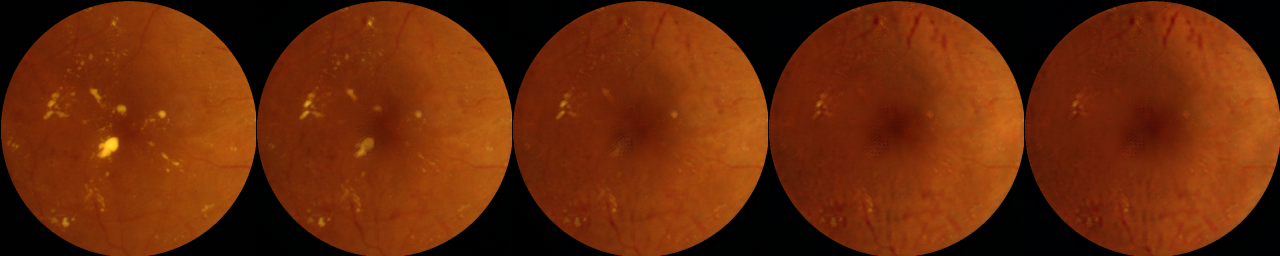

4. Amplification highlights hard exudates and brightening in macula. With confidence in our CycleGAN transformations we next qualitatively analyze the changes introduced by the model in Figure 6. With successive application of and two changes are observed:

hard exudates are either added (for ) or removed (for ) consistently.

fovea region is brightened (for ) or darkened (for ) consistently.

Hard exudates Fig 6 shows (right images) adds hard exudates (yellow lesions) to images and (left images) generally diminishes or removes hard exudates completely. This is in line with our expectations since hard exudates are correlated (although not perfectly) with DME diagnosis.

Fovea brightening. The other is a very subtle difference only visible with successive application and with the images best viewed as a gif or video. For transformations in (left images), in each subsequent image the fovea region gets darker than the surroundings. And in the fovea region gets progressively lighter. Although this change is amplified (visible to the human eye) only with successive applications of functions and , a single application appears enough to convince classifier (Table 1) that the classes have changed. This highlights one of the key features of our explanation method i.e we can amplify and enhance subtle changes to make them more human interpretable.